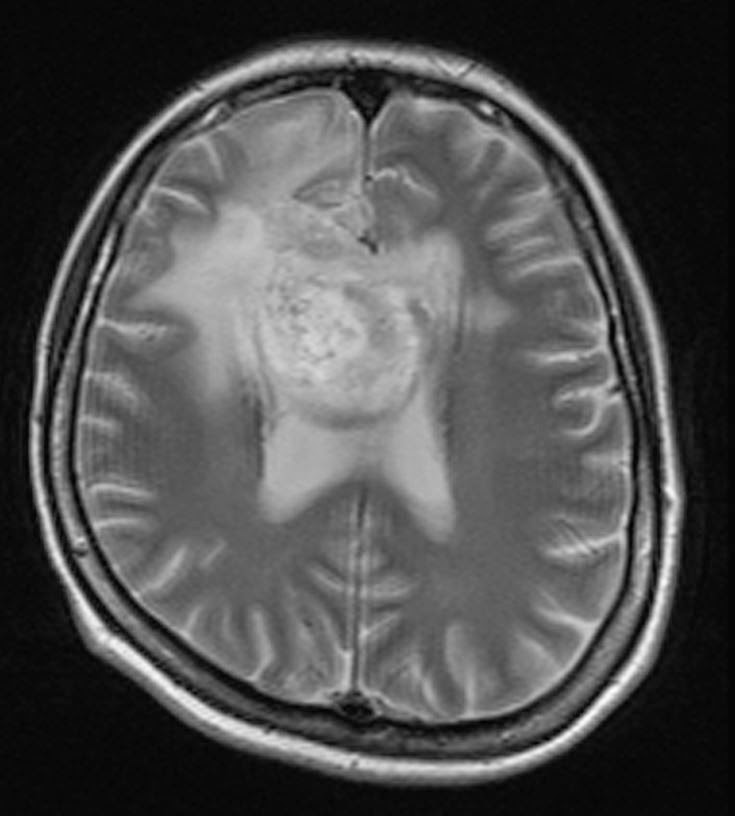

Összehasonlítva a 2014.02.10-i MR vizsgálattal:

A középvonalat balra kb. 1,5 cm-rel meghaladó és a corpus callosumot involváló jobb oldali frontalis inhomogén szerkeszetű és halmozású elváltozás mérete minden irányban mérsékelten csökkent, legnagyobb átmérője jelenleg kb. 5,6 x 5 x 4,7 cm. T2 súlyozásnál a laesio körül a hyperintenzitás kiterjedése főként dorsalis irányban enyhén csökkent. Az elülső frontalis műtéti behatolás mögött parasagittalisan a liquorhoz viszonyítva magasabb jelű bennéket tartalmazó cystosus elváltozás mérete hasonló a korábbihoz. Bal oldalon temporalis DVA* látható. A kamrarendszer frontális részeinek compressioja és dislocatioja lényegesen nem változott.

Vélemény: Enyhe méretcsökkenést mutató jobb túlsúlyú bifrontális tu. a corpus callosum infiltratiojaval.